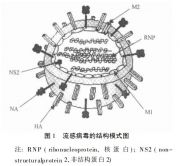

| 2021年7月26日 (一) 20:01 | 流感病毒.jpg (文件) |  |

55 KB | 77921020 | Uploaded with SimpleBatchUpload | 3 |